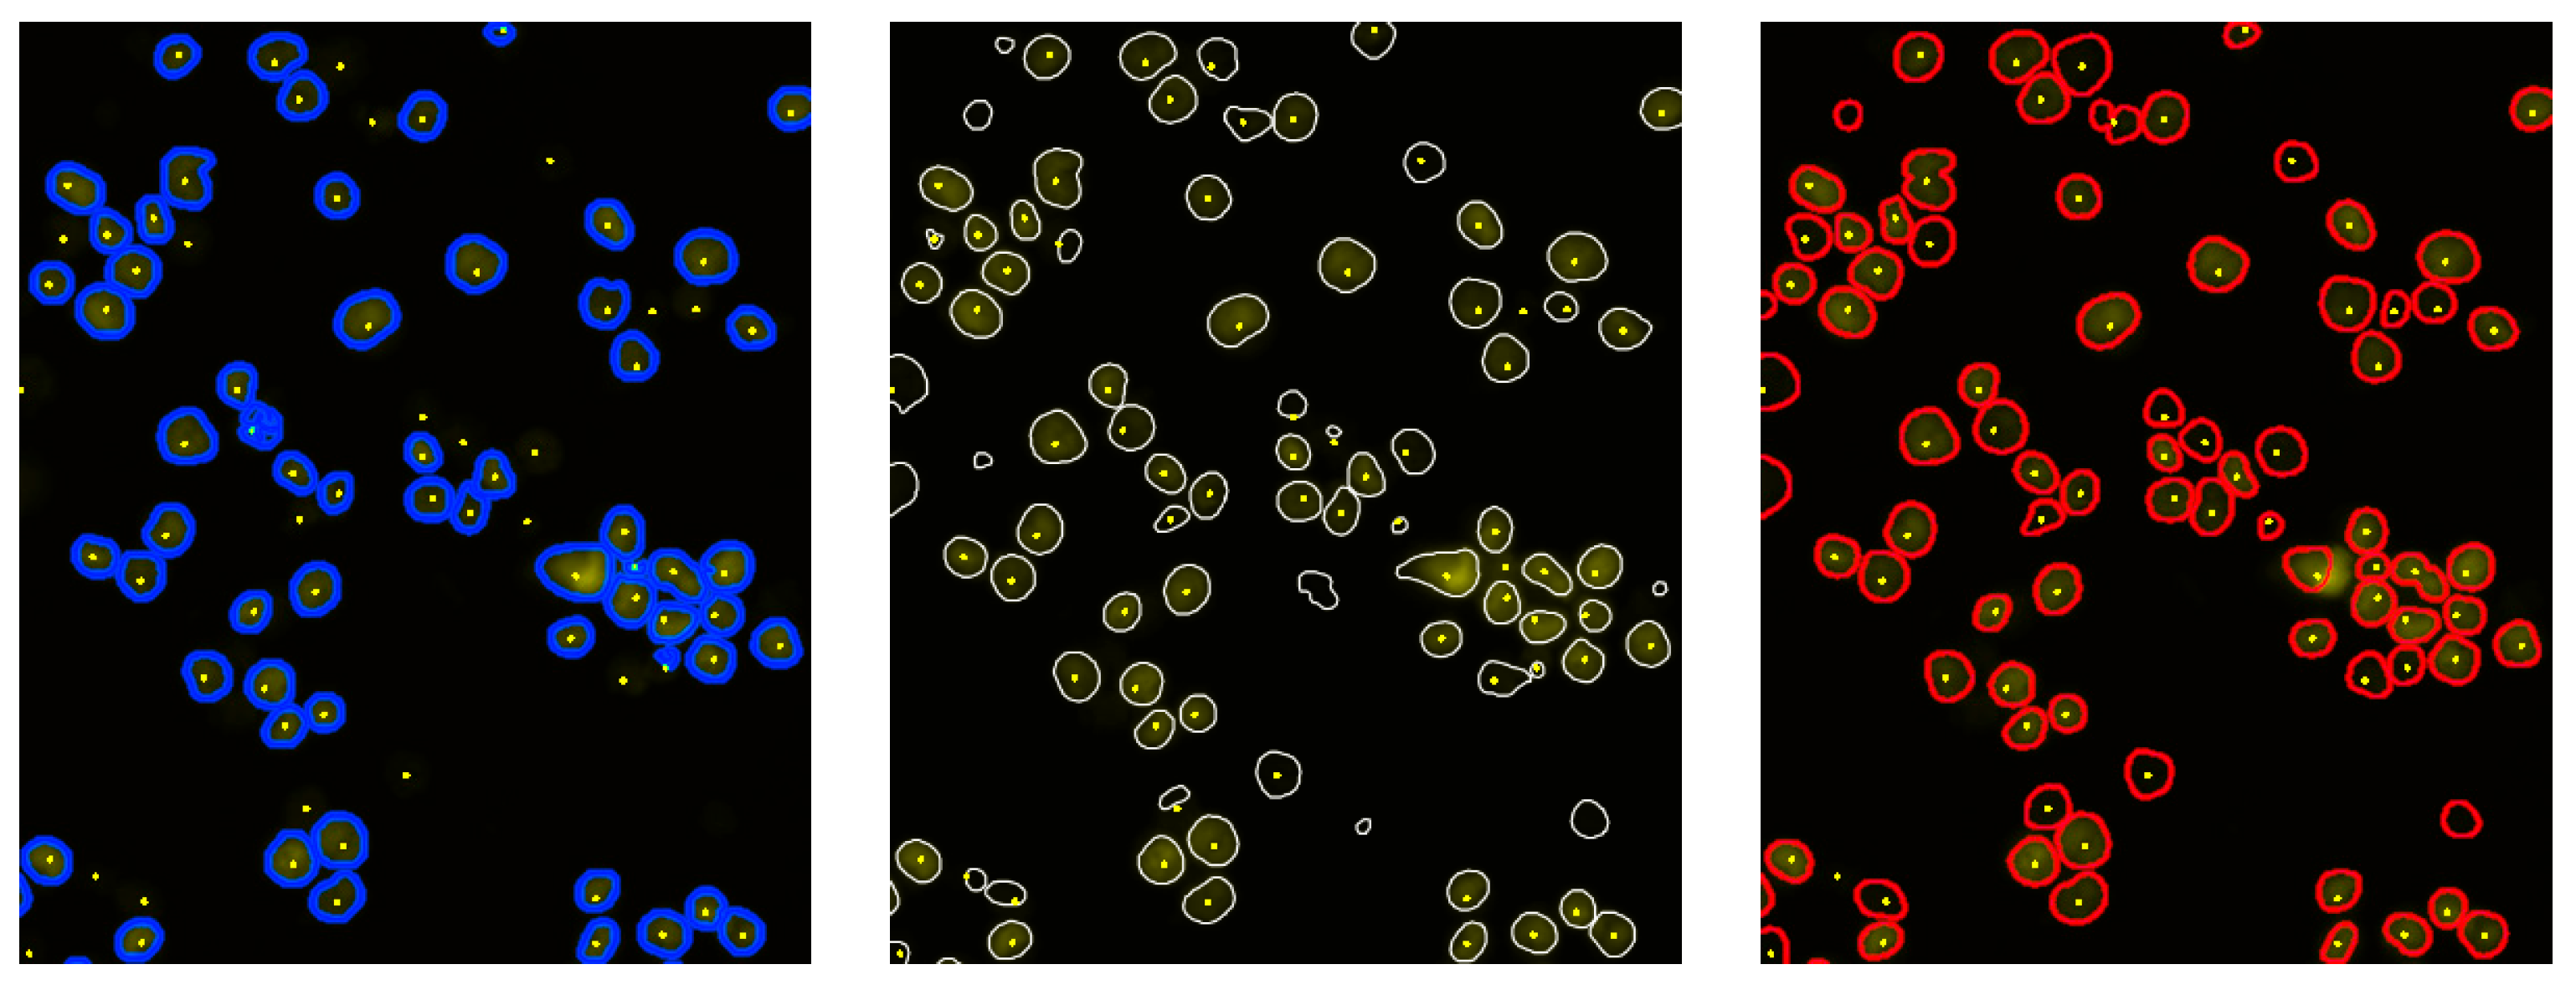

These algorithms were selected primarily to probe the complexity of the segmentation task, but these three algorithms also represent distinct inductive biases—threshold-based morphology, gradient space filtering, and learned shape priors—providing complementary error patterns for ensemble refinement. Table 1 summarizes their core principles, key characteristics, and relative computational complexity. Figure 2 contains a sample of the segmentation results of the three algorithms.

Figure 2. Segmentation results of Algorithms 1 (blue), 2 (white), and 3 (red), respectively, from left to right on the same region. Yellow spots are hand-placed annotations. Algorithms 2 and 3 are visibly more sensitive to weakly stained objects, with this also producing more false-positive finds.